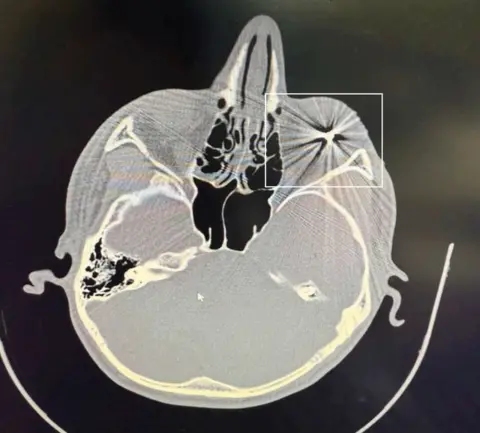

Obtained by BBC News Persian

An exclusive CT-scan image obtained by BBC News Persian shows a metal pellet embedded in a Mashad protester's right eyeball

As we saw during the crackdown on the 2022 Woman, Life, Freedom protests, the widespread use of shotguns in January resulted in the killing of many protesters and left hundreds, if not thousands, more with permanent eye injuries.

Between 9 and 10 January, about 1,000 patients needing emergency surgery for ruptured eyeballs caused by metal pellets arrived at a single eye hospital alone, its head, Dr Ghasem Fakhraei, told the semi-official Iranian Students' News Agency.

And BBC News Persian has obtained CT scans and medical records of several wounded protesters from Mashhad, one of which clearly shows a metal pellet embedded in the eye tissue.